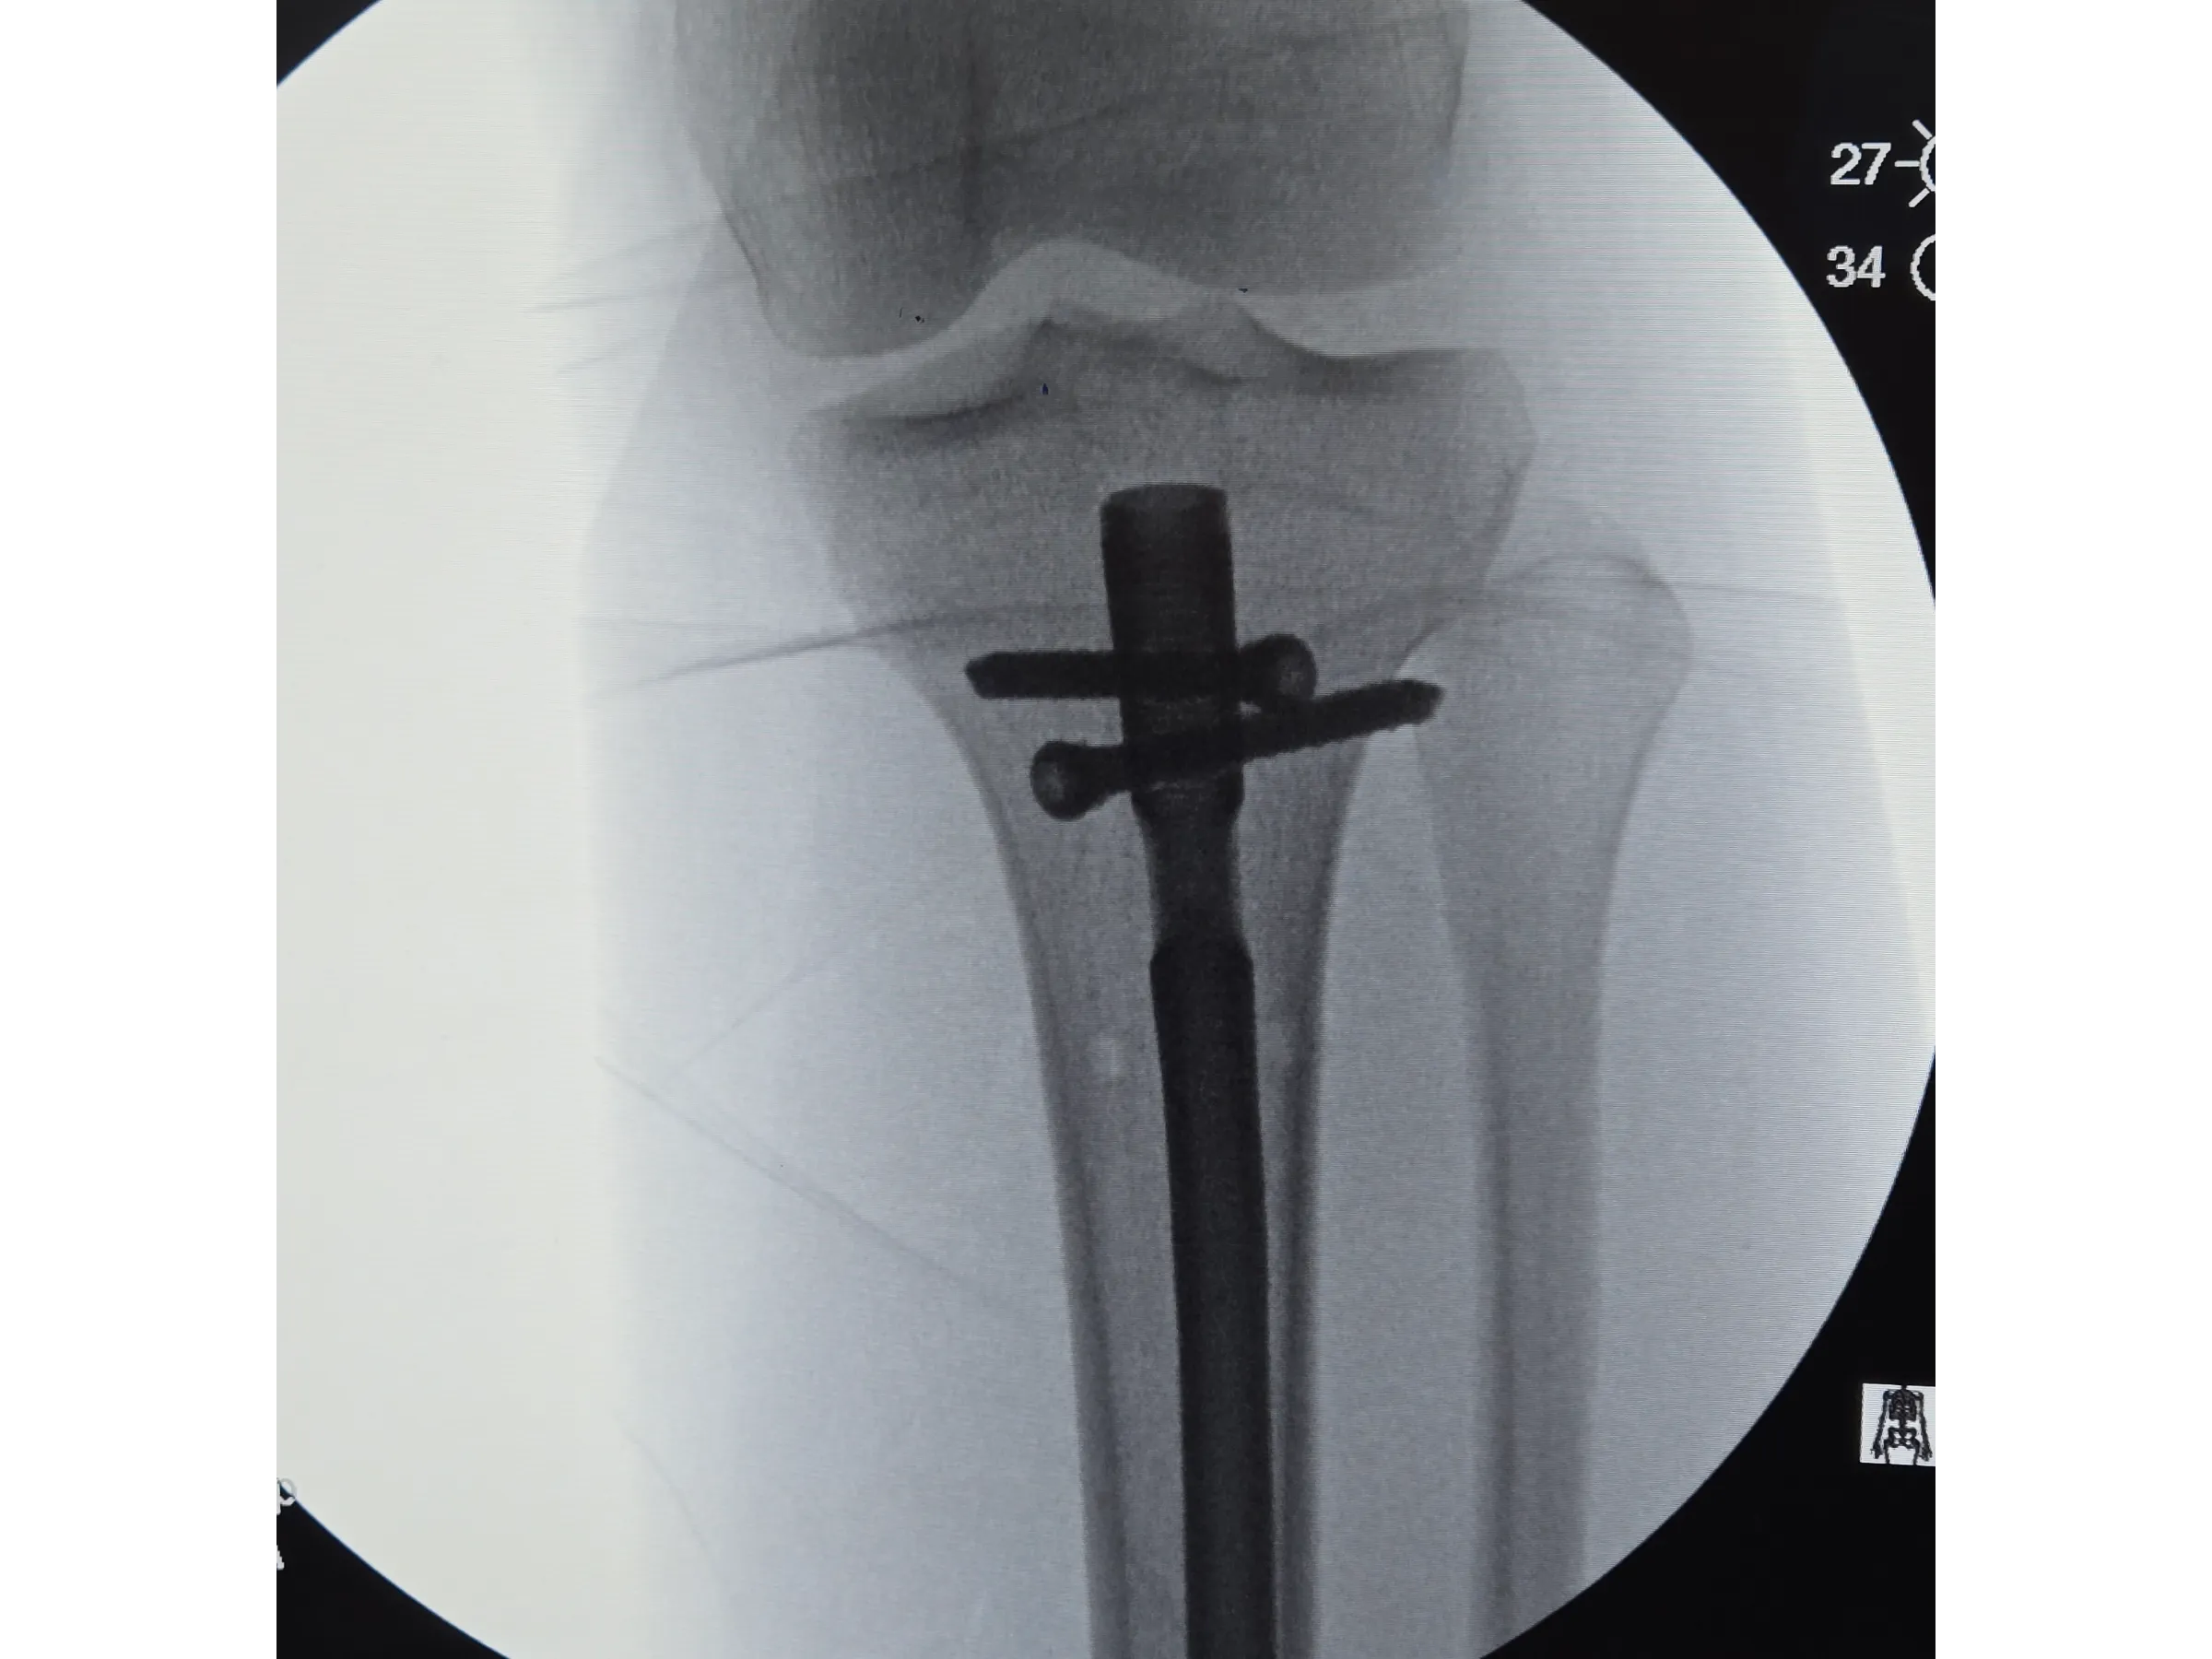

- Bloqueios proximais e distais com abordagem minimamente invasiva;

- Bloqueios Proximais e Distais Minimamente Invasivos: Execução de bloqueios cruzados e distais com pequenos portais e controle por intensificador;